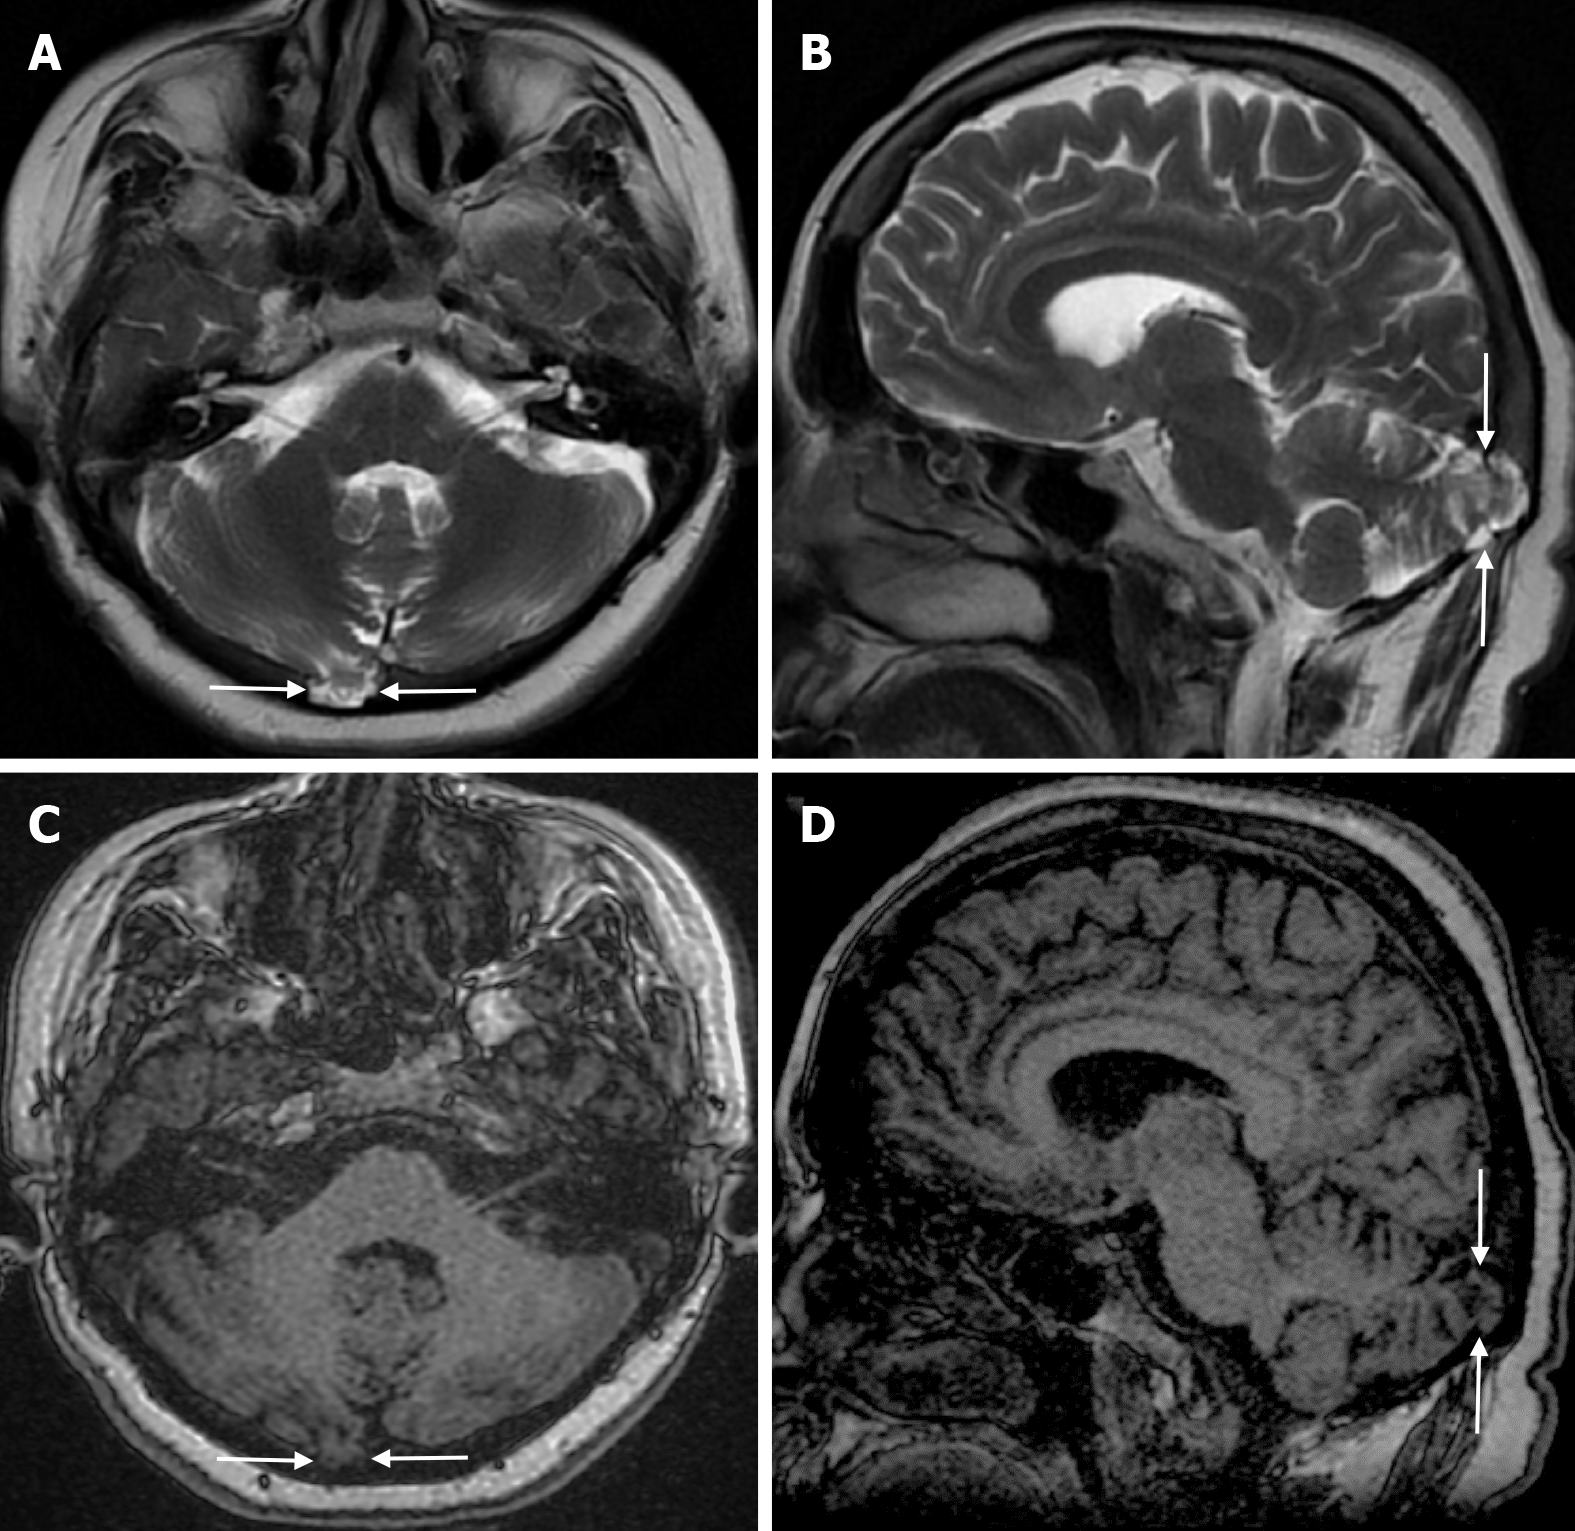

Arachnoid granulations (Pacchionian granulations) are cerebrospinal fluid-filled projections that extend from the subarachnoid space through openings in the dura into the venous sinuses and can be seen macroscopically. Their incidence varies from 0.3% to 55%. Arachnoid granulations are usually seen in millimeter dimensions, but may grow to fill the dural sinuses or arch the inner table[11]. In addition, intraosseous arachnoid granulations can sometimes extend to the inner table of the bone, causing scalloping, remodeling or bone erosion of the inner table[12]. The prevalence of arachnoid granulations increases with age, but there is no difference in gender distribution. Arachnoid granulations with a slight left hemispheric predominance are found in the dural venous sinuses, most frequently in the transverse sinuses and especially in the middle or lateral parts. The second most common location is the superior sagittal sinus, but they can be found anywhere in the dural venous sinuses. Arachnoid granulations are usually detected incidentally. If they fill and expand the dural sinuses, causing partial sinus obstruction, they may cause symptoms of increased intracranial pressure due to venous hypertension. They are usually associated with headaches. Arachnoid granulations may be seen as radiolucent areas on plain radiography of the skull or may cause compression on the inner table of the skull. On CT imaging, arachnoid granulations can be seen as sharply demarcated, hypodense structures in close relation to the dural venous sinus. On MRI, they usually show hyperintense signal on T2-weighted images and hypointense or isointense signal on T1-weighted images compared to brain parenchyma (Figure 1). On CT angiography, MR angiography or catheter angiography imaging, arachnoid granulations appear as oval or round filling defects in the dural venous sinuses during the venous phase[11]. Recent advances in radiology have made it possible to identify brain herniations into the arachnoid granulation by improving image quality with higher resolution and thinner slice three-dimensional T1-weighted and T2-weighted MRI sequences (Figure 2). Brain herniation into the arachnoid granulation is rare in the literature, and the incidence of brain herniation into the calvarial or dural sinuses has been reported to be 0.32%[13]. Arachnoid granulations may be confused with pathological processes in the dural venous sinuses[11]. In the differential diagnosis of arachnoid granulations, venous sinus thrombosis, dural-based tumors, or structures such as septa and fat that may cause filling defects in the dural venous sinuses should be considered[12]. Dural sinus thrombosis usually fills an entire sinus segment or several sinuses and may extend to the cortical veins, whereas arachnoid granulations appear as focal and well-defined defects. Fresh thrombus in the dural sinuses are hyperdense on CT and hyperintense on T1-weighted MRI. Differential tumor diagnosis can be made based on its shape, lack of contrast enhancement and diffusion restriction[11].

The beaten copper skull shows prominent convolutional markings on several bones of the skull. These convolutional markings normally appear between the ages of 2-3 and 5-7 years, which are periods of rapid brain growth. The occurrence of convolutional markings in children younger than 18 months should suggest a cause leading to increased intracranial pressure due to processes such as obstructive hydrocephalus, craniosynostosis or intracranial masses. Beaten copper skull pattern develops because of pressure applied to the soft skull by the growing brain. The beaten copper skull is usually confined to the posterior part of the inner table of the skull, but this appearance can affect the entire skull. Plain radiography of the skull can be an important diagnostic tool to detect increased intracranial pressure. In children, CT and three-dimensional reconstructions are best used to evaluate the convolutional markings (Figure 5) and cerebral ridges for surgical planning[23].

Atretic encephalocele is a midline scalp mass covered by skin containing meninges and neural remnants and/or degenerated brain tissue. In atretic encephaloceles, the brain tissue in the scalp degenerates and may remain attached to the dura mater by a fibrous stalk intracranially. Atretic cephaloceles may be associated with a persistent falcine vein characterized by a vertical embryonic position of the straight sinüs (Figure 6). Most atretic encephaloceles are parietal in location. On CT imaging, a subgaleal soft tissue mass may be seen in a “spinning top” configuration. CT imaging helps visualize bone defects, while MRI helps determine the contents of the encephalocele[3]. The lesions most commonly confused with atretic encephaloceles are sinus pericranii and dermoid cysts[25].

Sinus pericranii is a rare vascular anomaly with transosseous venous channels connecting the intracranial venous system to the extracranial veins[26]. It is usually congenital, but trauma is thought to be a predisposing factor. The congenital lesion has an endothelial lining, while the acquired lesion has a connective tissue lining. The male to female ratio is 2/1 and the condition can be seen in all age groups, but is usually diagnosed before the age of 30. Sinus pericranii is most commonly located near the midline. The frontal region is most commonly involved, followed by the parietal and occipital regions, while lateral localization is rare[27]. Sinus pericranii is often associated with other intracranial venous anomalies, such as developmental venous anomalies or venous vascular malformations. Affected patients typically present with a soft cutaneous mass that expands in the supine position or during the Valsalva manoeuvre and contracts on standing. Patients are usually asymptomatic, but headache, dizziness or nausea may occasionally occur. Sinus pericranii is classified as dominant (the majority of venous flow communicates with the sinus pericranii) or accessory (only a portion of intracranial venous flow communicates with the sinus pericranii). CT venography shows a calvarial defect and anomalous communication between the dural venous sinus and the extracranial veins (Figure 7). Thrombosis of the dominant sinus pericranii, where most intracranial venous drainage occurs, is associated with life-threatening complications such as venous congestion and/or infarction. Treatment is contraindicated in the dominant type. For accessory sinus pericranii, interventional (i.e. surgical or endovascular) treatment may be indicated to improve symptoms, prevent future traumatic haemorrhage and air embolism, and for cosmetic reasons[26]. Sinus pericranii should be suspected when a soft, fluctuant mass is detected near the intracranial sinus and can vary in size. MRI shows the relationship of the lesion to the underlying sinus, while direct injection of contrast medium through the wall of the mass shows rapid passage of contrast into the sinus[27]. Also, MRI shows variable signal intensity due to flow artefacts[26].